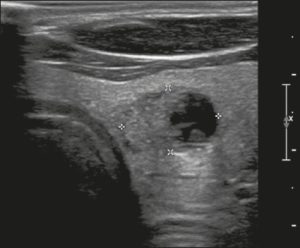

Ở đây, chúng tôi cung cấp các ví dụ minh họa việc áp dụng thực tế hệ thống ACR TI-RADS (Hình 18, 19, 20, 21). Các chú thích dưới hình mô tả chi tiết các mục đã được đánh giá và hiển thị điểm số trong ngoặc đơn.

Hình 19. Hình ảnh nhân giáp dạng đặc (2 điểm), giảm âm rất mạnh (3 điểm), rộng hơn cao (0 điểm), có bờ trơn láng (0 điểm), và không có các ổ tăng âm hay bóng lưng (0 điểm). Do đó, tổng điểm là 5 điểm và mức độ nguy cơ được phân loại là TR4.